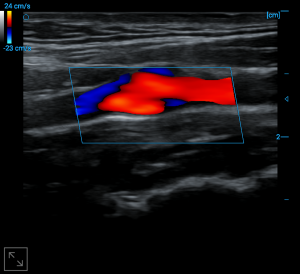

Carotid bulb blood flow

PW auto trace